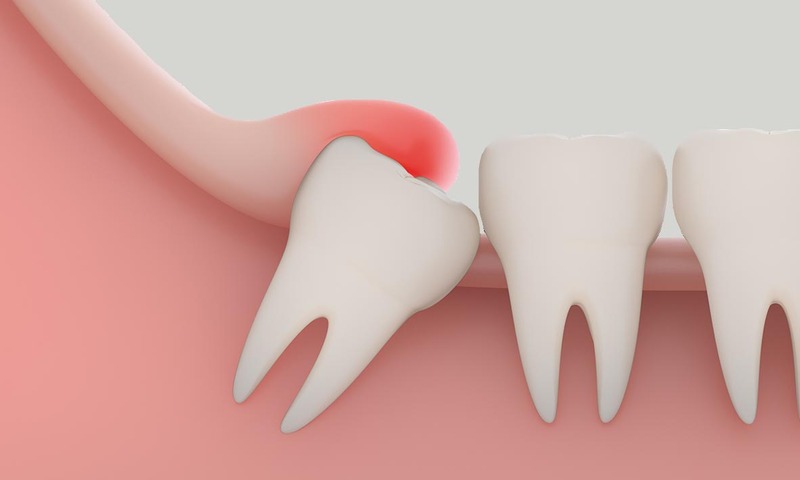

Đau nhức vùng góc hàm: Đây là triệu chứng đầu tiên và phổ biến nhất. Cơn đau thường bắt đầu âm ỉ ở vùng nướu trong cùng, sau đó tăng dần mức độ và tần suất. Khi răng khôn mọc lệch đâm vào xương hoặc răng bên cạnh, cơn đau có thể lan lên tai, thái dương và gây đau đầu dữ dội, khiến bạn mất ăn mất ngủ.

Sưng tấy và viêm nướu: Vùng nướu bao phủ phía trên răng khôn thường bị sưng đỏ, căng mọng và rất nhạy cảm khi chạm vào. Do răng mọc lệch tạo ra những kẽ hở khó vệ sinh, vi khuẩn dễ dàng tích tụ gây ra tình trạng viêm lợi trùm. Trong nhiều trường hợp, vùng nướu bị viêm có thể tiết dịch mủ và có mùi hôi khó chịu.

Hủy hoại răng số 7: Đây là biến chứng đáng sợ nhất mà Xanh Dental thường xuyên gặp phải. Răng khôn mọc lệch đâm trực tiếp vào răng số 7, gây sâu răng, viêm tủy hoặc tiêu xương chân răng số 7. Răng số 7 là răng ăn nhai chủ lực trên cung hàm, nếu mất đi chiếc răng này, chức năng ăn nhai của bạn sẽ bị giảm sút nghiêm trọng.